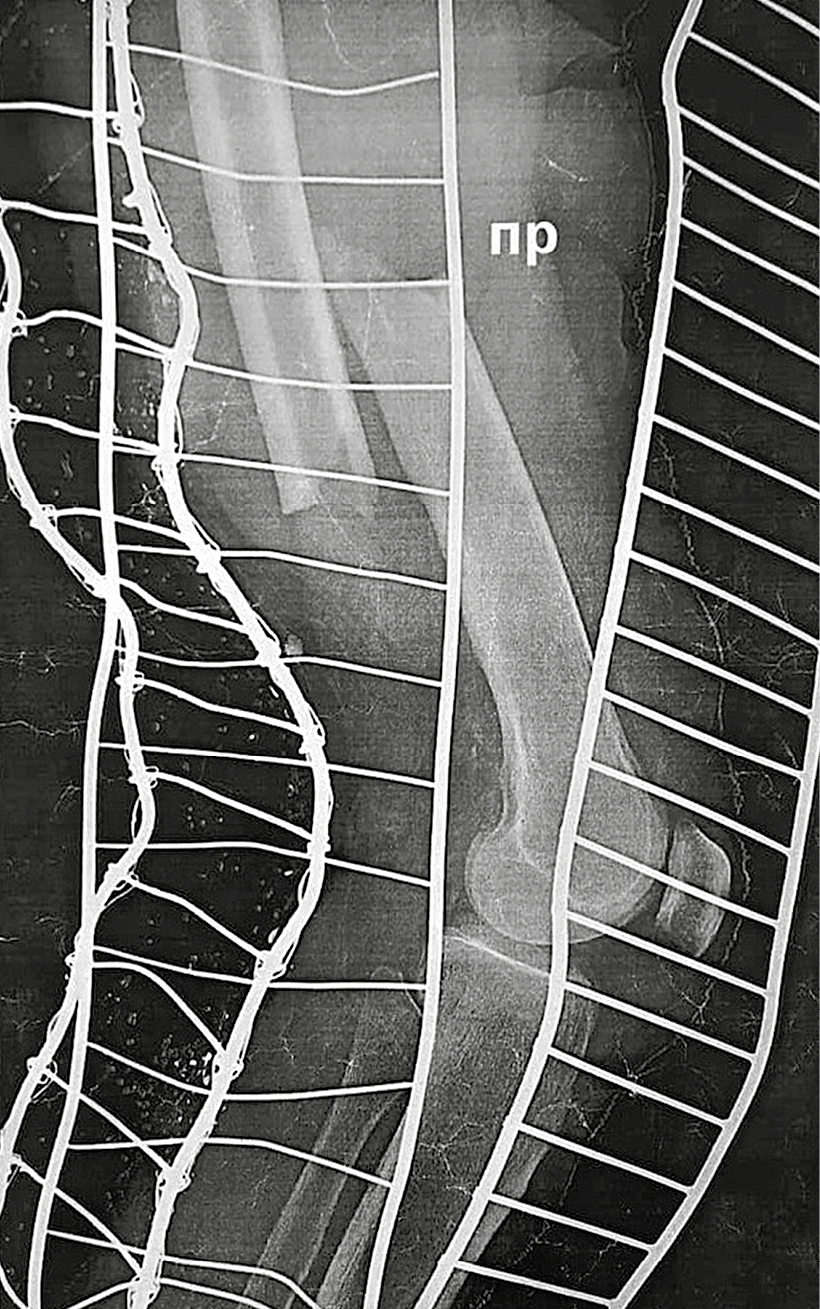

A 78-year-old woman, receiving oral bisphosphonate for severe postmenopausal osteoporosis for 3.5 years, suddenly started feeling pain in her right thigh while walking. Three months later, she had got a fracture in middle third of the right femur after falling from her standing height. According to instrumental diagnostics, this fracture had all criteria of AFF. Blocking intramedullary osteosynthesis with shafts was performed. A retrospective analysis of soft tissue magnetic resonance imaging in the area of right thigh, done before the fracture, showed the presence of undiagnosed incomplete right femur fracture in the middle third, which subsequently led to a complete fracture.

2. Fig. 2. Radiograph of the right lower limb of patient K. on the day of transverse diaphyseal atypical fracture of the right femur, type 42A1 according to the classification of the Osteosynthesis Association, dated 04.12.2017. | |